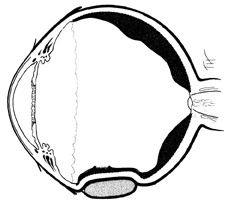

Tenon's capsule is a fascial tissue that invests both the globe and extraocular muscles. Anteriorly it fuses with conjunctiva at the limbus, and posteriorly it ends at the optic nerve sheath. Between Tenon's capsule and the sclera is the interfascial space of Tenon, or simply Tenon's space. Entering this space allows complete exposure of the scleral surface. The extraocular muscles pass through Tenon's capsule, entering Tenon's space to insert on the sclera. At the site of penetration by the individual extraocular muscles, Tenon's capsule reflects posteriorly around the muscles for 10 to 12 mm to form the muscle sheaths. The muscle sheaths are connected by the intermuscular membrane, which, in turn, is connected to the orbital wall by complex fascial arrangements. The retinal surgeon is most concerned with the extraocular muscles after they pass through Tenon's capsule (Fig. 1). At this point they do not possess a muscle sheath but, rather, are invested by episcleral tissue that fuses with the muscle. This tissue forms the falciform folds that fan out from the edges of the muscle to the overlying Tenon's capsule (Fig. 2).

Fig. 1. Anatomy of Tenon's capsule and extraocular muscles.